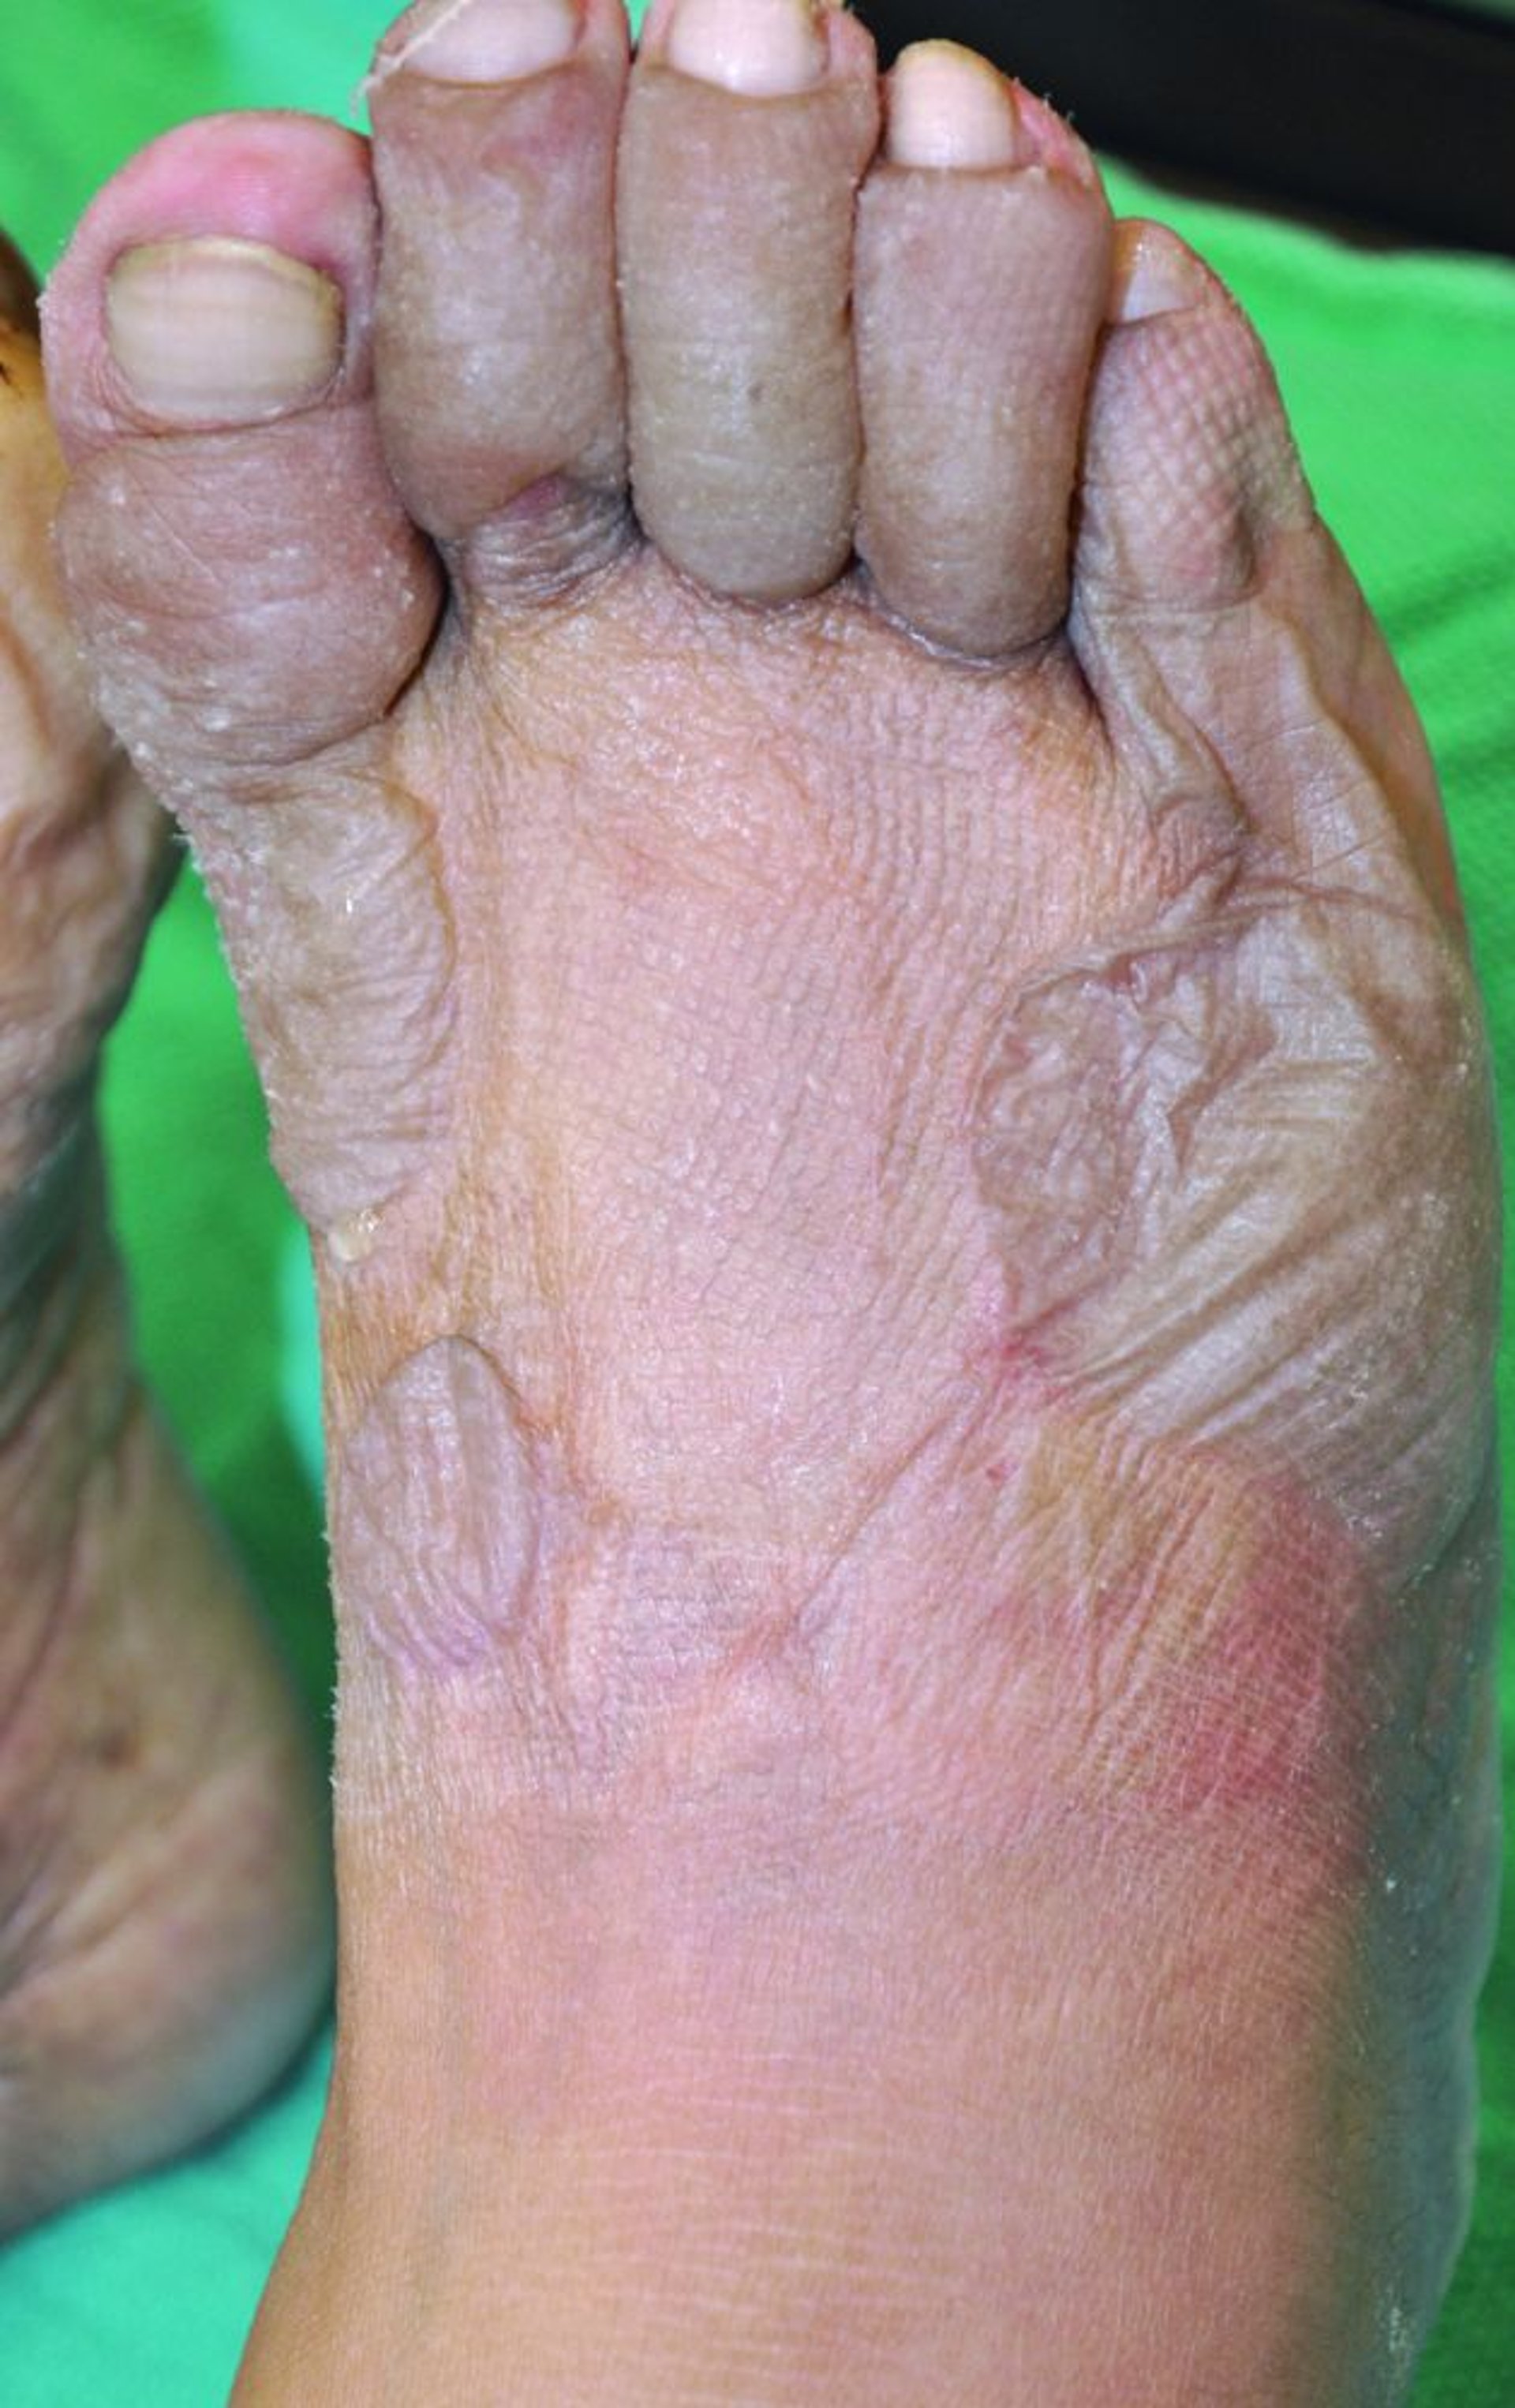

Gelure du pied

Cette photo montre des ongles pâles, des orteils gris œdémateux et des bulles sur le pied. L'absence de sang dans les bulles suggère que les engelures sont superficielles et qu'une perte tissulaire résiduelle est peu probable après la guérison.